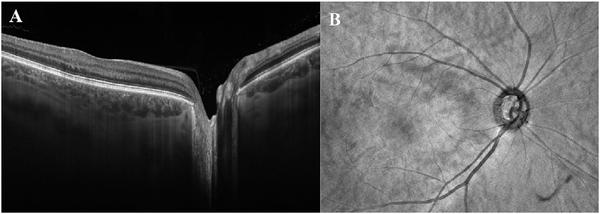

Optical coherence tomography (OCT) was one of the biggest advances in ophthalmic imaging. Building on that platform, OCT angiography (OCTA) provides depth resolved images of blood flow in the retina and choroid with levels of detail far exceeding that obtained with older forms of imaging. This new modality is challenging because of the need for new equipment and processing techniques, current limitations of imaging capability, and rapid advancements in both imaging and in our understanding of the imaging and applicable pathophysiology of the retina and choroid. These factors lead to a steep learning curve, even for those with a working understanding dye-based ocular angiography. All for a method of imaging that is a little more than 10 years old. This review begins with a historical account of the development of OCTA, and the methods used in OCTA, including signal processing, image generation, and display techniques. This forms the basis to understand what OCTA images show as well as how image artifacts arise. The anatomy and imaging of specific vascular layers of the eye are reviewed. The integration of OCTA in multimodal imaging in the evaluation of retinal vascular occlusive diseases, diabetic retinopathy, uveitis, inherited diseases, age-related macular degeneration, and disorders of the optic nerve is presented. OCTA is an exciting, disruptive technology. Its use is rapidly expanding in clinical practice as well as for research into the pathophysiology of diseases of the posterior pole.

光学相干断层扫描(OCT)是眼科成像领域的重大突破之一。在此基础上,OCT 血管造影术(OCTA)提供了视网膜和脉络膜血流的深度分辨图像,其细节水平远远超过了旧的成像方式。这种新的模式具有挑战性,因为需要新的设备和处理技术,目前成像能力的限制,以及成像和对视网膜和脉络膜成像及适用病理生理学的理解的快速发展。这些因素导致学习曲线陡峭,即使对于那些对基于染料的眼部血管造影术有一定了解的人来说也是如此。所有这些都是为了一种成像方法,它的历史还不到 10 年。这篇综述从 OCTA 的发展历史和 OCTA 中使用的方法开始,包括信号处理、图像生成和显示技术。这是理解 OCTA 图像显示内容以及图像伪影产生原因的基础。本文还回顾了眼部特定血管层的解剖结构和成像。介绍了 OCTA 在评估视网膜血管阻塞性疾病、糖尿病性视网膜病变、葡萄膜炎、遗传性疾病、年龄相关性黄斑变性和视神经疾病的多模态成像中的整合。OCTA 是一种令人兴奋的、颠覆性的技术。它在临床实践中的应用以及对后极部疾病病理生理学的研究中迅速扩展。